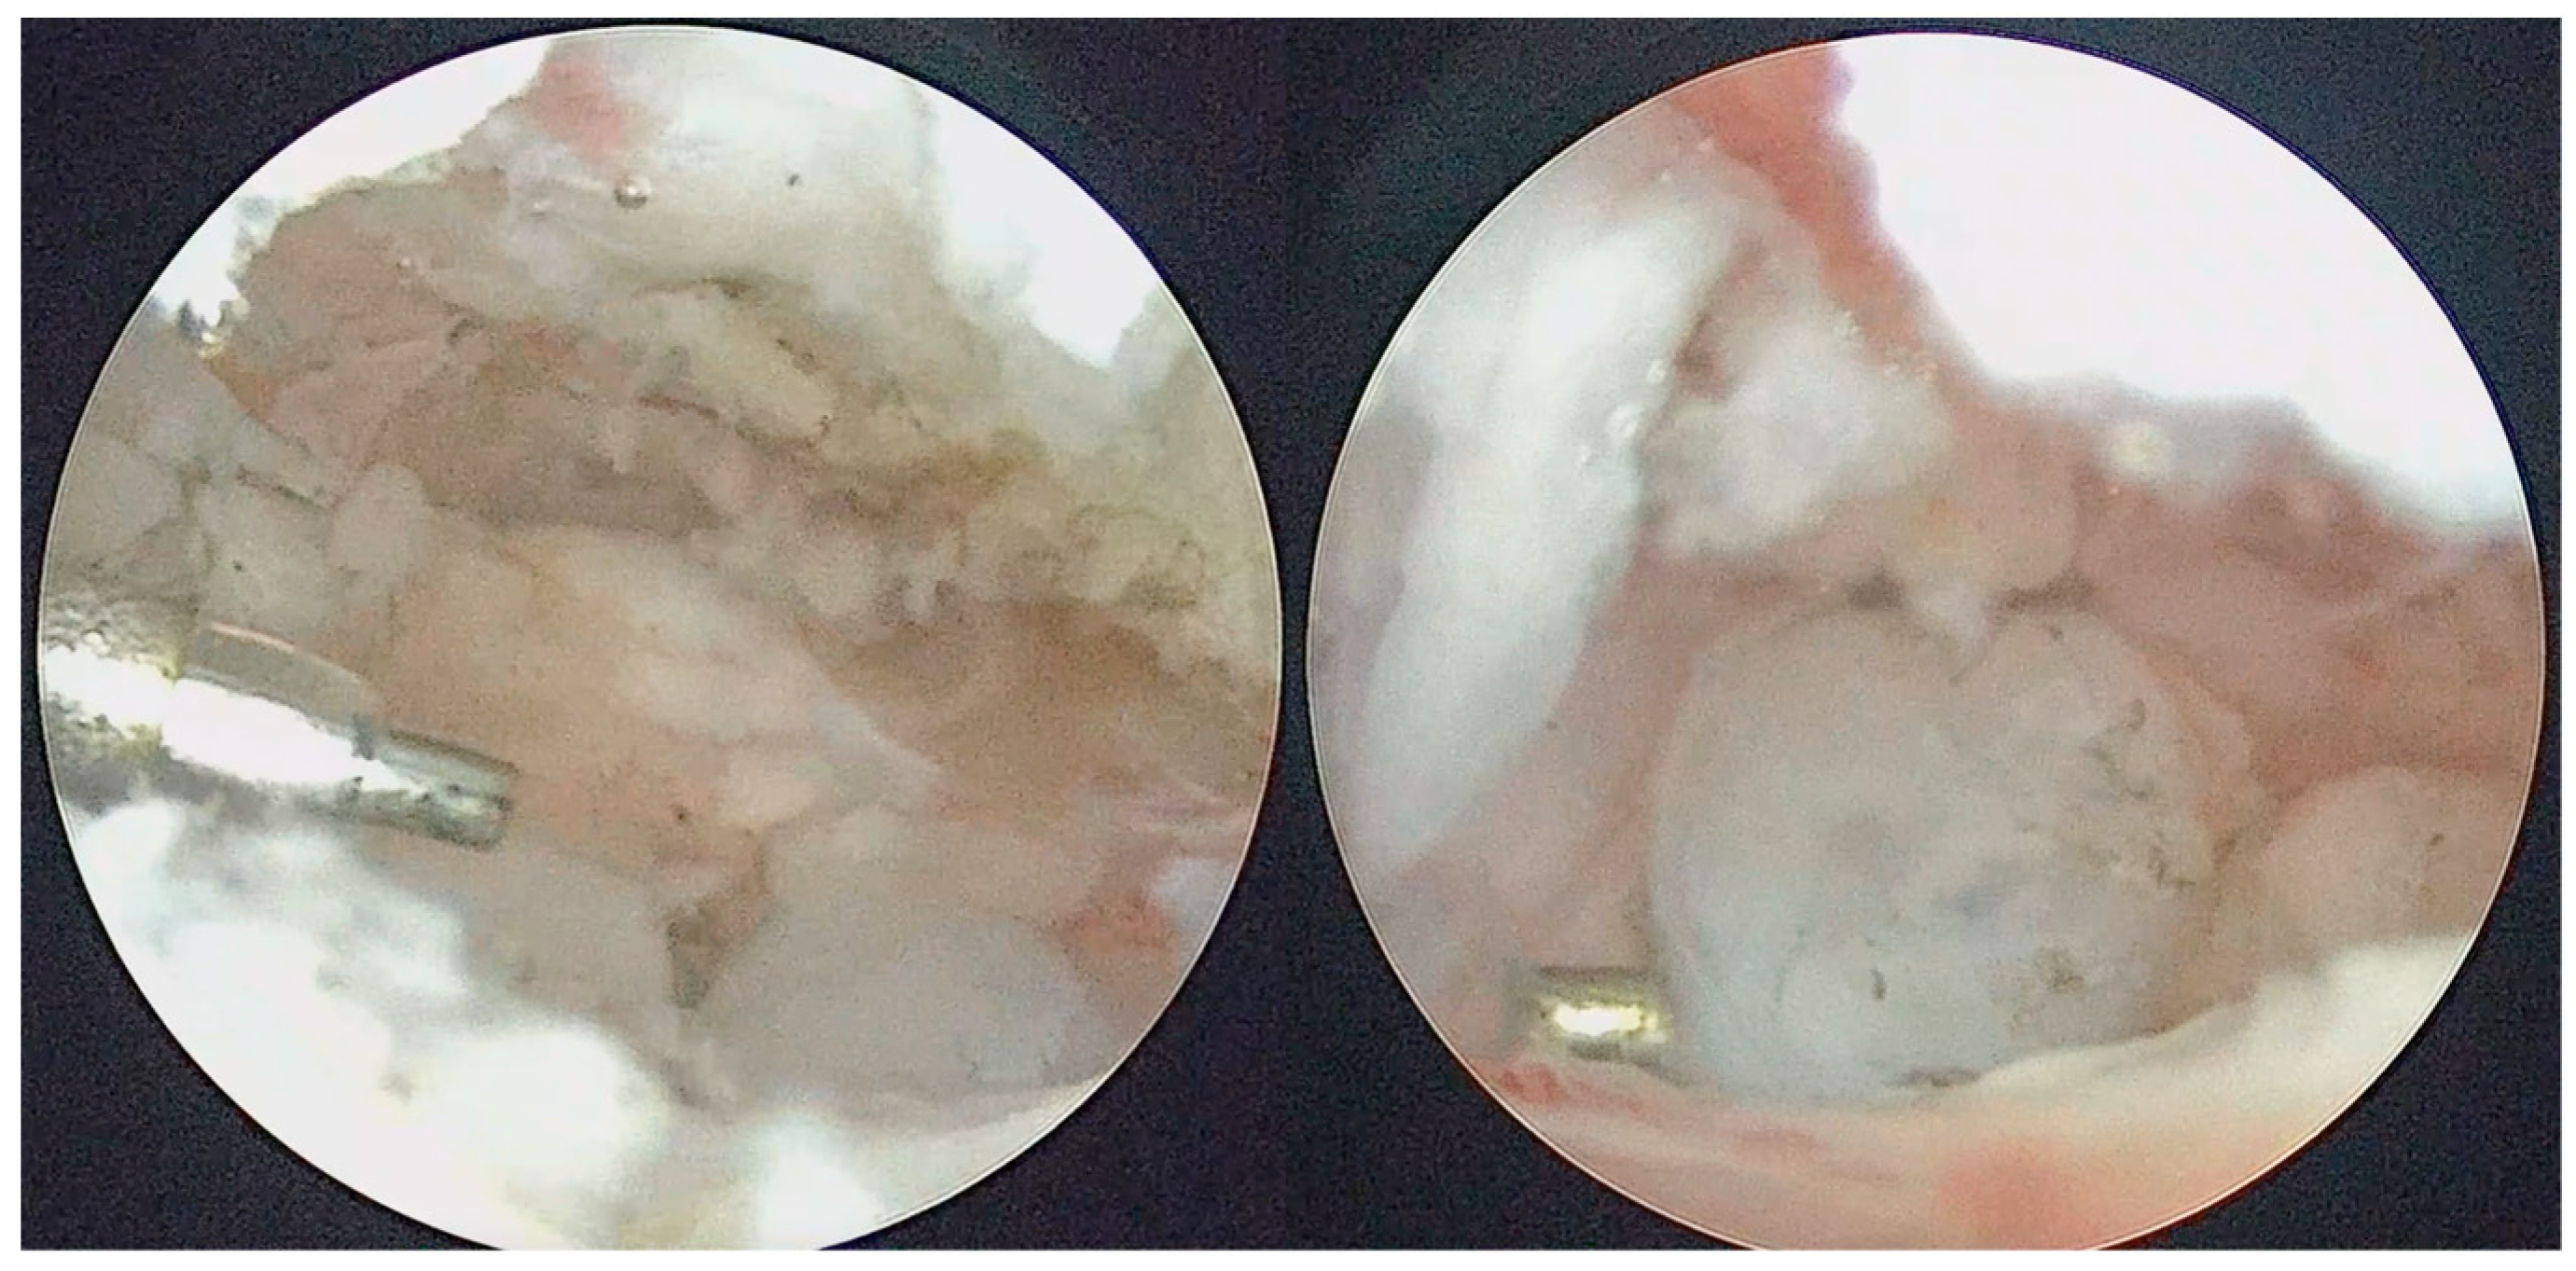

Figure 8.

LB sample sent for histopathological analysis.